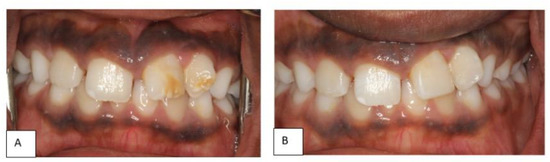

2.1. Clinical Examination and Diagnosis

2.2. Treatment Plan and Progress